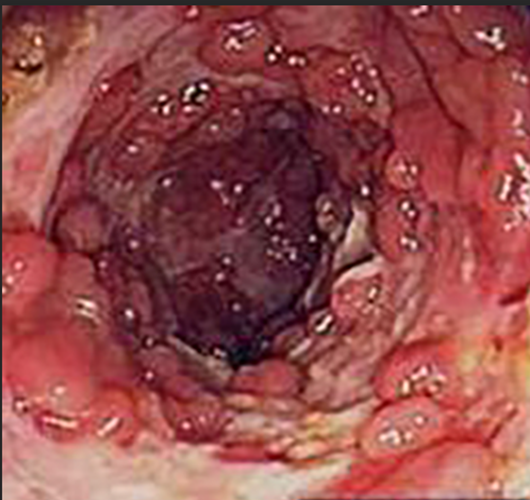

炎症性胃息肉

炎症胃息肉什麼症狀

炎症胃息肉

炎性胃息肉

炎性胃息肉切除

炎性胃息肉

炎性胃息肉的症狀表現